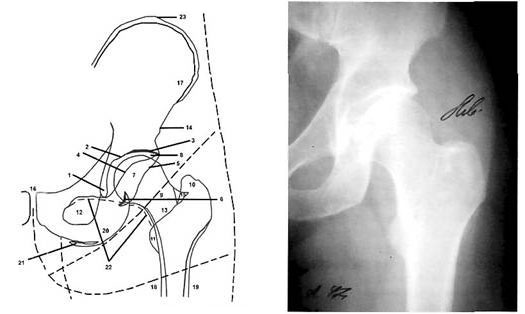

На рисунке 6 представлена схема типичной картины последствий перенесенного артрита (как правило, ревматоидного) тазобедренного сустава. Имеется нарушение нормальных соотношений в тазобедренном суставе в обратном обычному подвывиху направлении, а именно: слишком большое погружение головки в вертлужную впадину - тело седалищной кости в области «фигуры слезы» резко истончено и продавлено внутрь, часть дна вертлужной впадины проецируется кнутри от пограничной линии. При этом «фигура полумесяца» накладывается не на медиальный квадрант головки, а на более латеральный ее отдел. Наблюдаются резкое сужение рентгенологической суставной щели, остеопороз головки бедренной кости, краевые оссификаты головки на месте ее контакта с краями вертлужной впадины.

Рис. 6. Схема рентгенограммы тазобедренного сустава с признаками протрузионного коксартроза: 1 - крыша вертлужной впадины; 2 - дорсальная часть внутренней стенки малого таза в области тел подвздошной и седалищной костей; 3 - ость седалищной кости; 4 - пограничная линия; 5 - «фигура слезы»; 6 - «фигура полумесяца» (дно седалищно-суставной борозды); 7 - головка бедренной кости; 8 - шейка бедренной кости (из руководства Майковой-Строгановой B.C., Рохлина Д.Г., 1957).

При дальнейшей нагрузке происходит постепенная деформация головки бедренной кости; она смещается вверх, ротируется кнаружи и приводится, что клинически соответствует развитию стойкой сгибательно-приводящей контрактуры сустава (рис. 8).

Рис. 8. Рентгенограмма больного с двухсторонним диспластическим коксартрозом III ст. Деформация и подвывих головок бедренных костей, резкое сужение суставных щелей, остеофиты нижних полюсов вертлужных впадин и головок бедренных костей, остеосклероз нагружаемых отделов крыши вертлужной впадины.